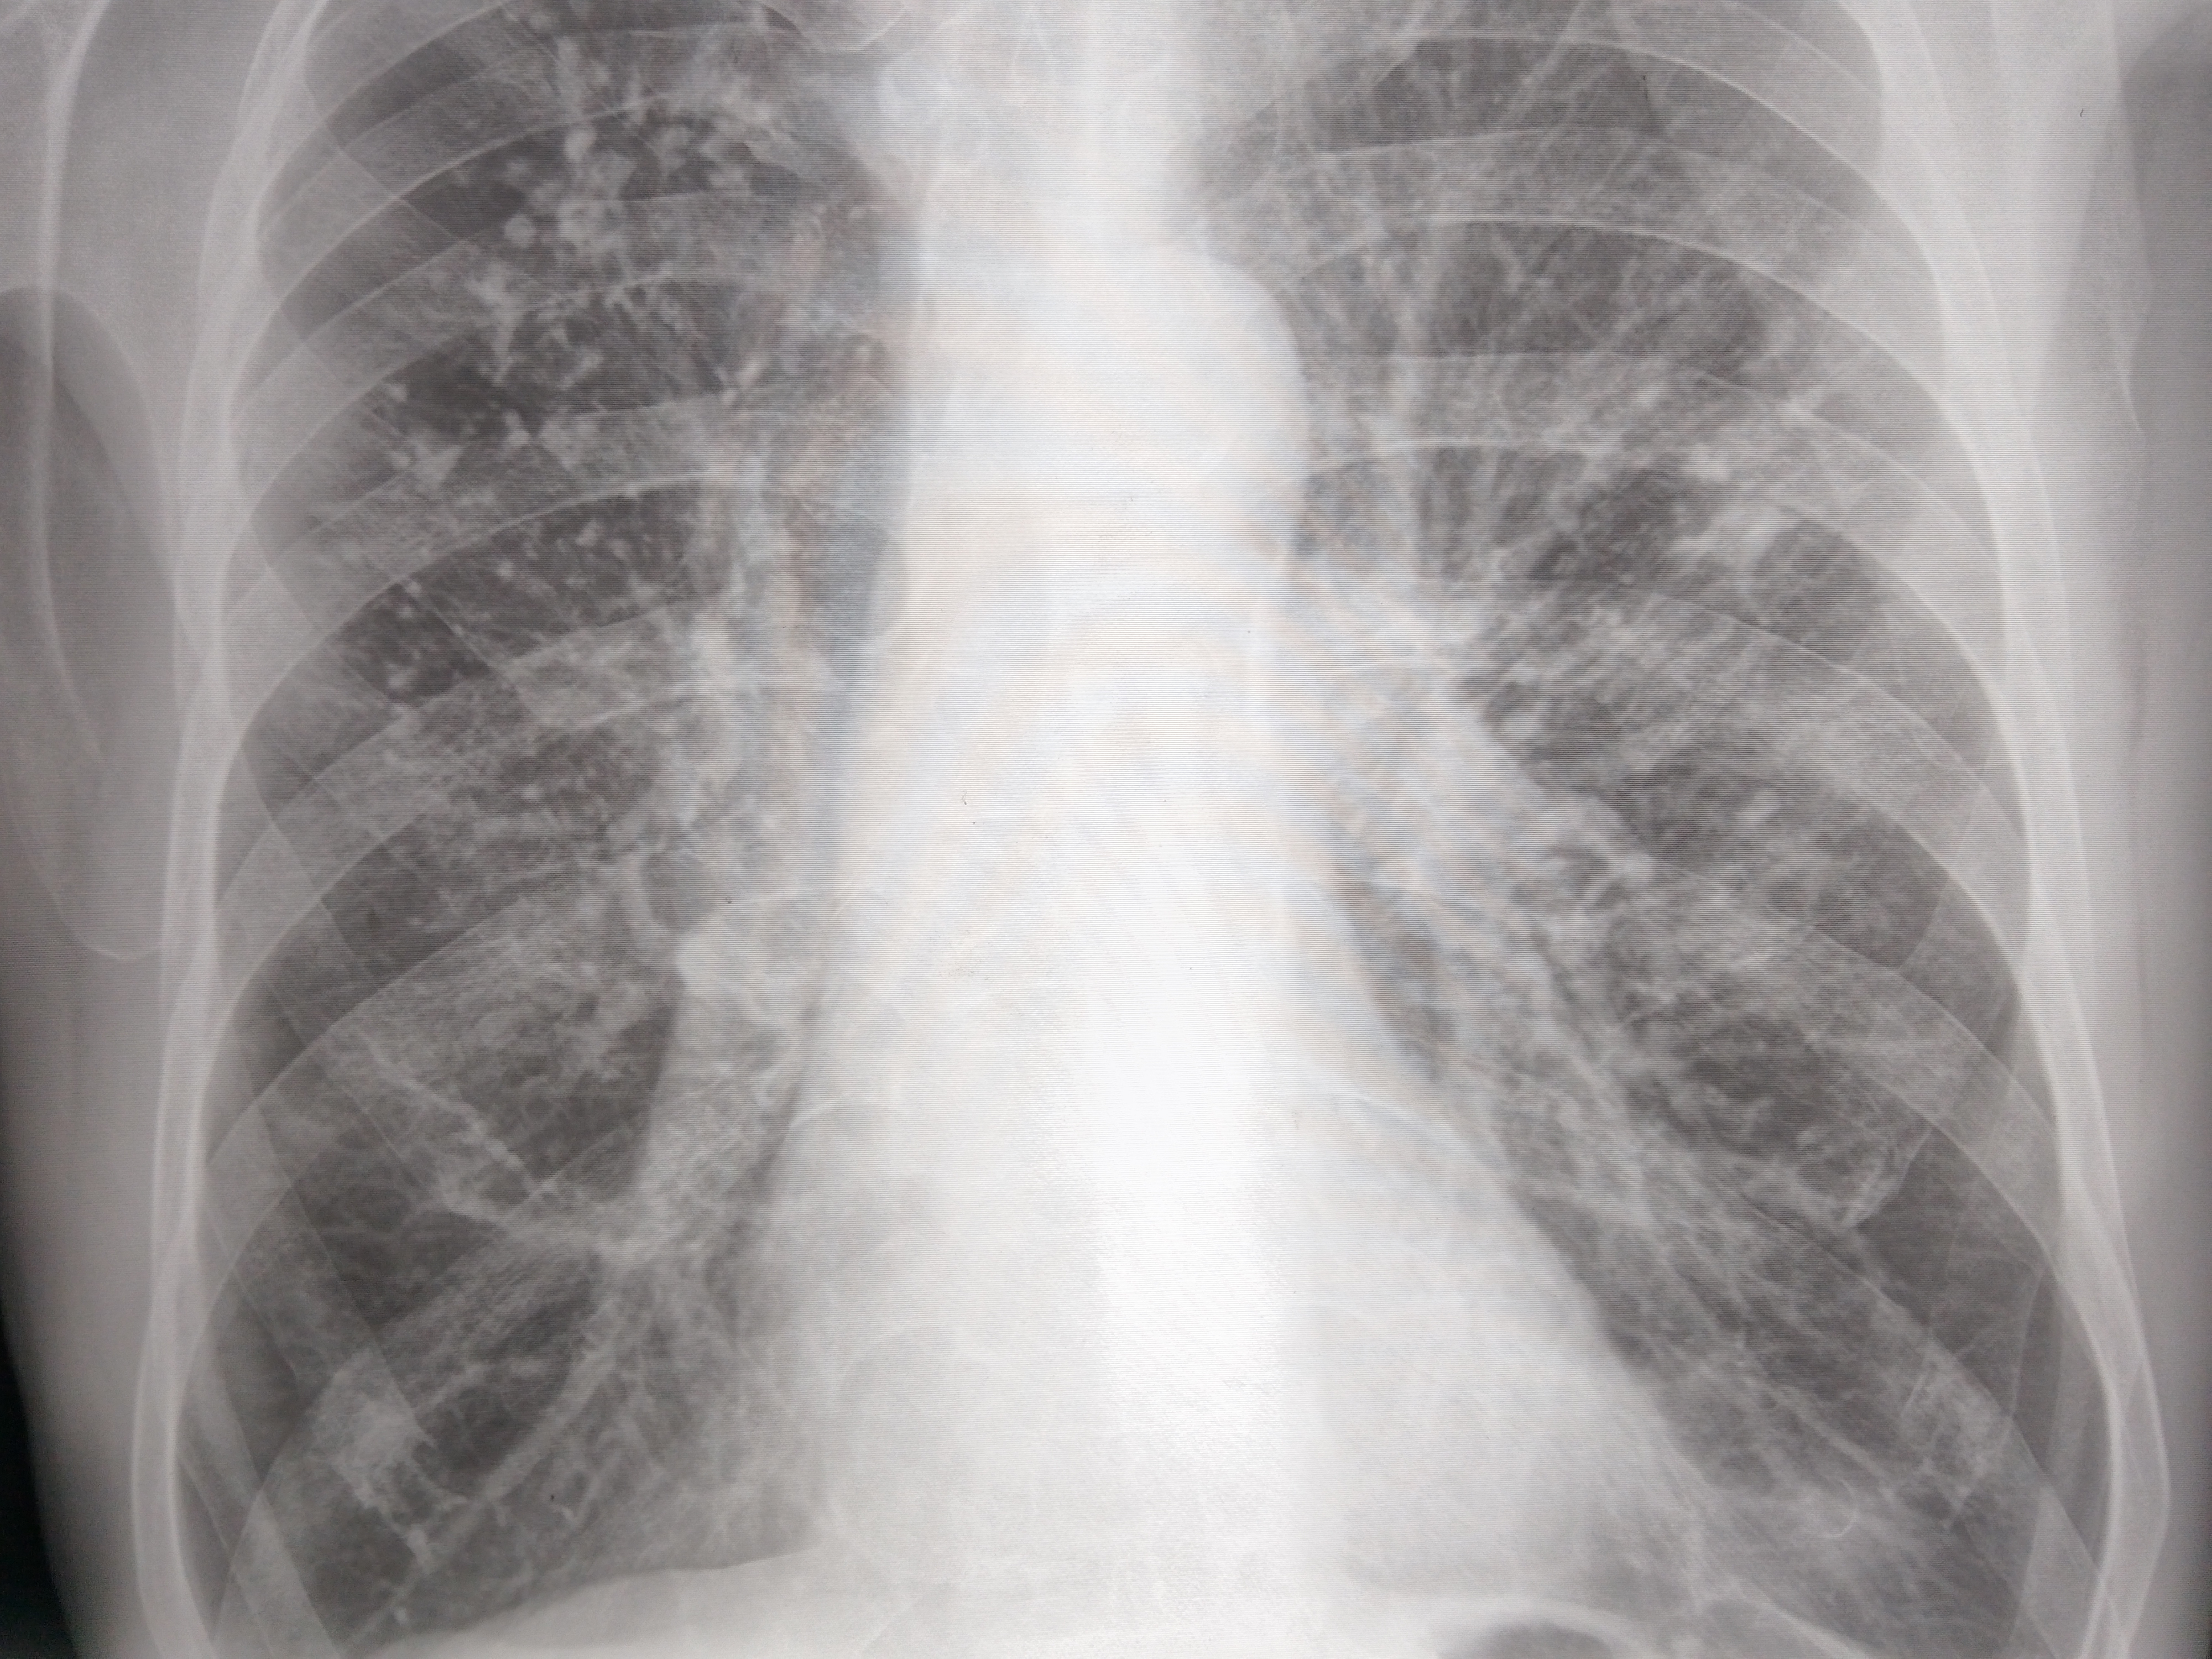

Никогда такой хуйни не было! И вот опять! Здравствуй двачик! Я итт буду с вами играть в рентгенолога, флексить зарплатой 31 к за октябрь и общатся! Давайте дружить! Угадывайте пиздецомы по фоточке и общайтесь ибо я тут чо-то заебалс. Штош погнали!